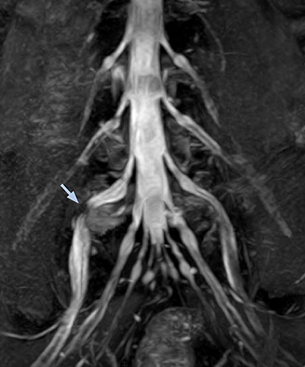

“In such case, we would then browse through axial T2-weighted MR images slice by slice and mentally reconstruct the actual situation based on both radiculography and MRI. Fortunately, NerveVIEW can now very well show nerve courses and presence of nerve compression or edema in one single image series.” “We have often seen NerveVIEW directly depict details of the nerve compression that were not observed by radiculography. Therefore, we think that with NerveVIEW we can reduce the number of invasive examinations, especially for some patients with lumbar plexus symptoms.”

“The intra-luminal signal of veins, especially around the intervertebral space, can be suppressed well with NerveVIEW. As a result, we can easily observe the detailed nerve structure around the posterior ganglion,” he says. “This is why we use 3D NerveVIEW for intraforaminal stenosis and extraforaminal stenosis/herniation (lateral disc herniation). On the other hand, if herniation is suspected to exist inside the dorsal root ganglion (DRG), balanced TFE or ProSet-FFE is applied. NerveVIEW is not suitable for evaluating the median type of herniation.” The SE-EPI DWI-based method for MR neurography works well for large FOV exams like whole-body MRI, but focal examination of nerves is often limited by the attainable spatial resolution (both inplane and slice direction) and geometric distortion. “3D NerveVIEW achieves higher in-plane resolution – close to our other routine spine sequences – and the source images can be used instead of adding a fat-suppressed T2-weighted sequence,” Tanji says.

According to Tanji, methods such as ProSet FFE, STIR or 3D VISTA are anatomically nonselective because background signals, for instance from blood vessels, often interfere with nerves, which hampers evaluation of details, especially at the peripheral side of the nerves.